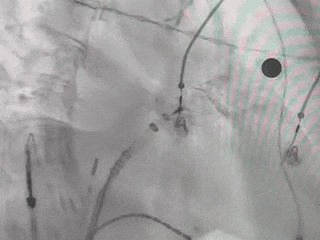

MemoLefort封堵器术中释放后造影评估

封堵器完全释放

肝位造影确认,封堵器位置合适,无残余漏

Lefort封堵器释放

Lefort封堵器评估符合PASS原则,释放封堵器,封堵器位置稳定且未见残余漏,封堵完美。